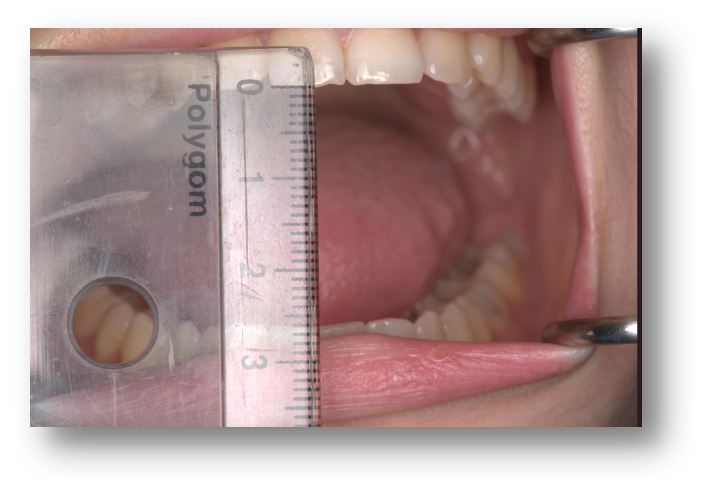

During clinical examination, mouth opening was restricted to 29.4 mm (measured using MetiSmile) and 27+4 mm (using the conventional ruler method) .

Figure 1: Opening measured using the conventional technique.

The application of mild force failed to increase the opening. A deviation to the right side was present during mouth opening. The patient reported pain in the right TMJ during left lateral excursions. Left lateral movement was 3.6 mm, while right lateral movement was 10.6 mm, carried out without pain. Protrusion was measured at 5.8 mm. Both opening and protrusion provoked a report of “familiar pain.” The patient self-assessed the pain level using a Visual Analog Scale (VAS), scoring 7 out of 10.